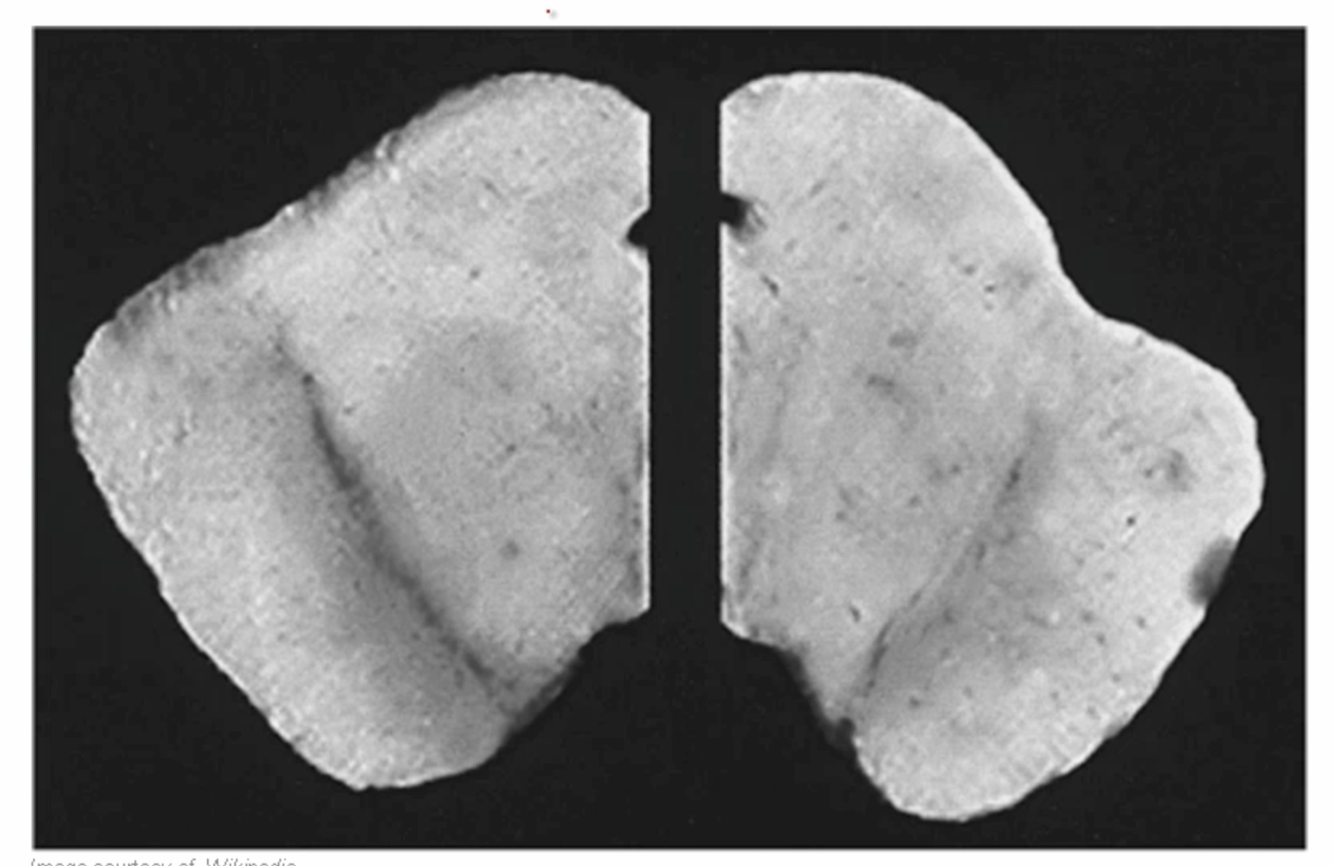

diag?

Follicular thyroid adenoma (this is toxic type, not nodule) -s\consists of single palpable nodule, benign

-Histology is follicular